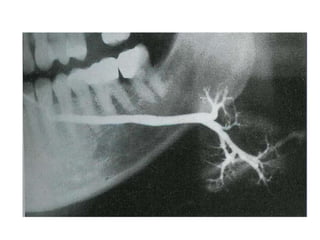

• The duct obstruction, destruction of glandular

tissue, and duct dilatation (sialectasia) may be

demonstrated by sialography.

• Other investigations useful in assessing the

are usually reduced, and sialography, which

shows varying degrees of sialectasis often

producing a 'snowstorm' or 'cherry tree in

blossom'-like appearance.

• Sialography will show sialectasis